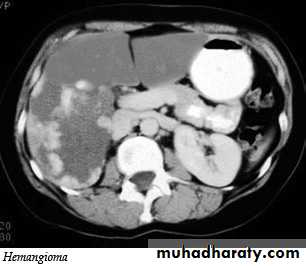

Hemangiomas of the liver

They are the commonest benign tumors in liver. They are common incidental finding and rarely requires treatment. It may cause significant hemorrhage, especially after trauma ,so percutaneous biopsy should be avoided. Hemangiomas are typically well-defined, peripheral echogenic masses at US. At CT, there is usually a characteristic peripheral, nodular and centripetal enhancement after IV contrast. MRI shows uniform very high signal intensity on T2 images.Liver abscess